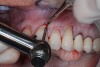

The graft is undermined by making an incision into the connective tissue layer using a #15C scalpel, leaving the epithelial layer intact (Figure 2). The tissue can then be lifted away and freed from the palate (Figure 3), after which it can be trimmed as necessary and ultimately transplanted back to the patient. The palate is then covered with a positive-pressure stent worn by the patient continuously for 1 week postoperatively, except when cleaning the stent after eating. During the second week postoperatively, the patient wears the stent only when eating. The palate is expected to be fully healed after the second week and then no longer requires protection. Surgical dressing is placed on the graft recipient site to reduce postoperative discomfort and facilitate proper healing of the graft site.

Fig 2. The FGG is undermined by making an incision into the connective tissue layer, leaving the epithelial layer intact.